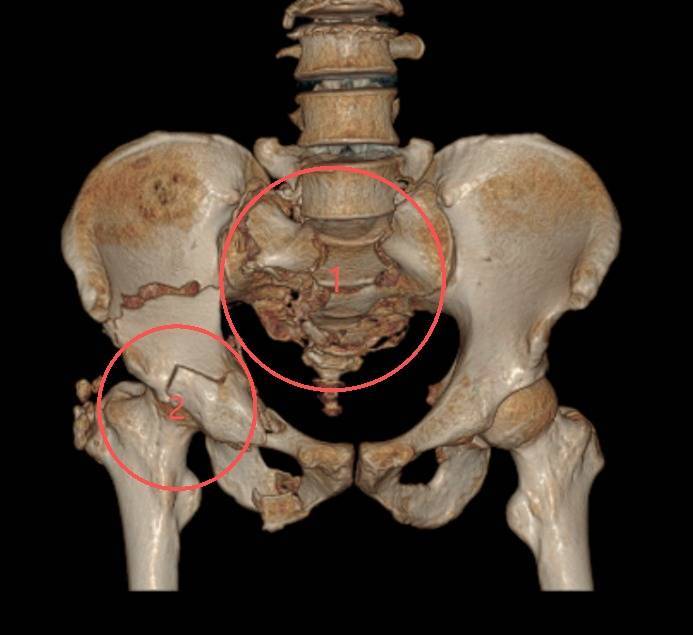

▲严重骨盆骨折,骶骨粉碎H型骨折,右侧髋臼骨折。图中“1”为骨盆后环骶骨严重粉碎性骨折,预示着高能量损伤,往往见于高处坠落伤,会引起致命性大出血和神经损伤;图中“2”为髋臼双柱骨折,治疗难度大,被称为创伤骨科的“皇冠级”手术。